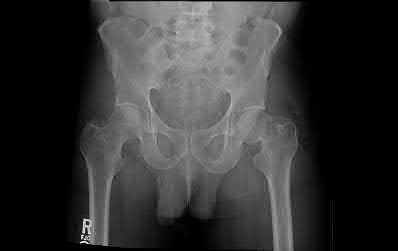

A 35-year-old man presents to the ED as the restrained driver of a high speed motor vehicle collision complaining of hip, chest, and abdominal pain. He becomes diaphoretic, tachycardic, and hypotensive in the trauma bay and is noted to have diminished lower extremity pulses. He is found on ATLS workup to have mediastinal widening.

Which of the following injuries is most associated with thoracic aortic injury?

Thoracic aortic rupture is associated with posterior hip dislocation in deceleration trauma mechanism of injuries.

Posterior hip dislocations are infrequently associated with local vascular injuries. With bilateral perfusion deficits, more proximal large vessel trauma should be considered, and in this situation, thoracic surgery should be involved emergently. Screening chest x-ray in the trauma bay should be reviewed for widened mediastinum, suggestive of aortic injury, as shown in illustration A. Given the high energy mechanism associated with these injuries, a full ATLS trauma survey must be done for every patient.

Marymont et al. studies the association between posterior hip dislocation and thoracic aortic injury. They performed a retrospective chart review of 89 posterior hip dislocations and found 8% had an aortic injury. Although not statistically significant, they note the importance of evaluation for aortic injury in patients with posterior hip dislocations given its emergent life-threatening nature.

Answer choices A,B,D,E show other injury patterns: Answer A - Right femoral neck fracture

Answer B - Right intertrochanteric hip fracture Answer D - Right subtrochanteric hip fracture

Answer E - Right superior and inferior pubic rami fractures